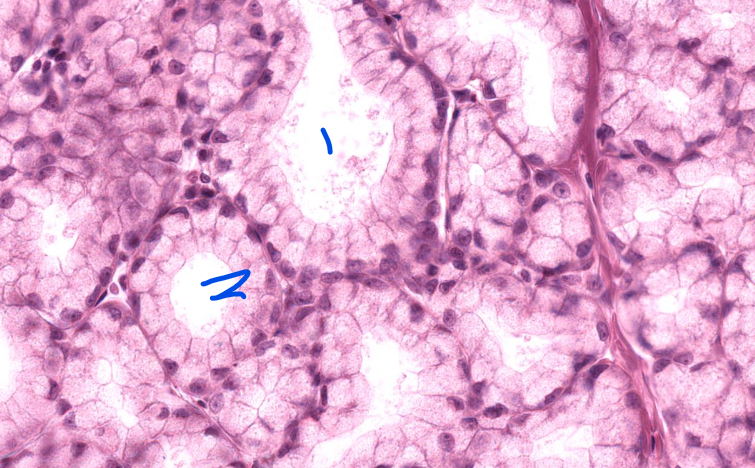

1

stratified squamous non-keratinized epithelium of esophagus

2

lamina propria of esophagus

3

muscularis mucosa of the esophagus